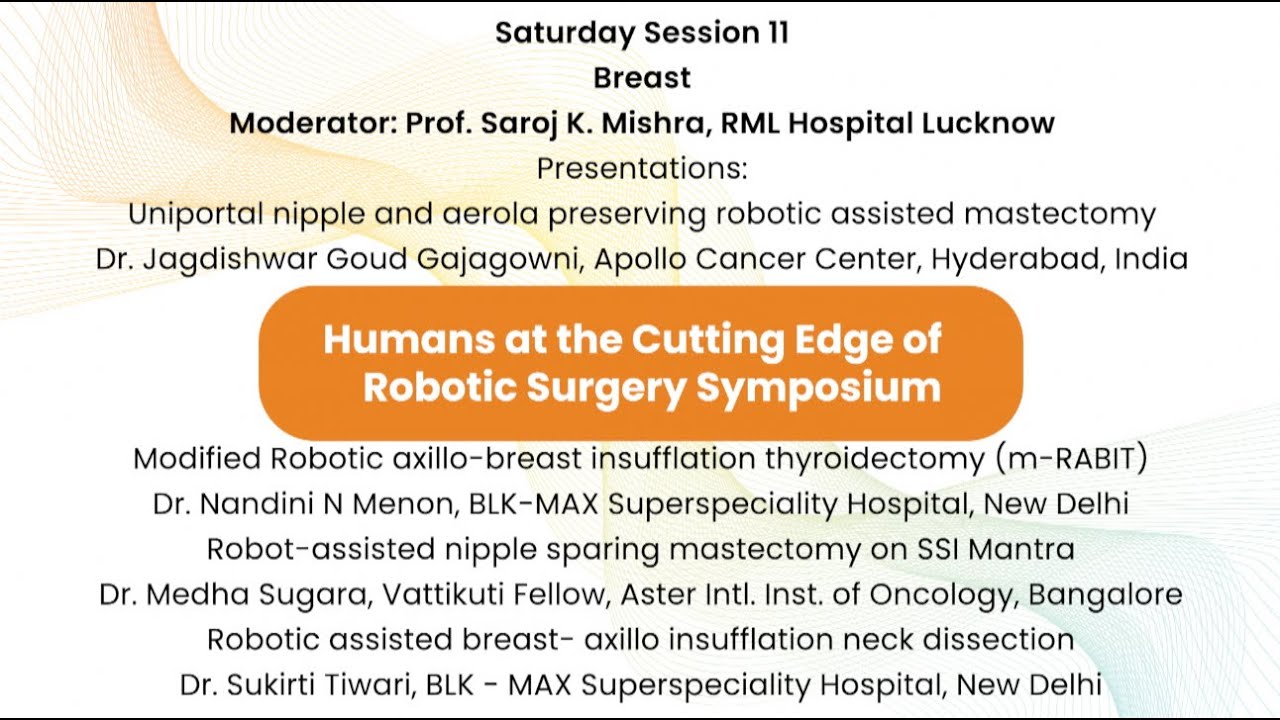

Jaipur Saturday Session 11 Breast

Humans of Robotic Surgery, KS Awards, Robotics, Surgeon, Video Library ';